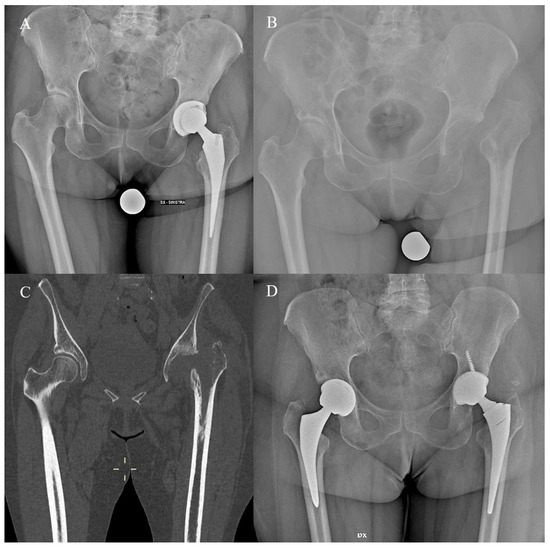

- Evola, F.R.; Evola, G.; Sessa, G. Use of short stems in revision of standard femoral stem: A case report. World J. Orthop. 2020, 11, 528–533. [Google Scholar] [CrossRef]